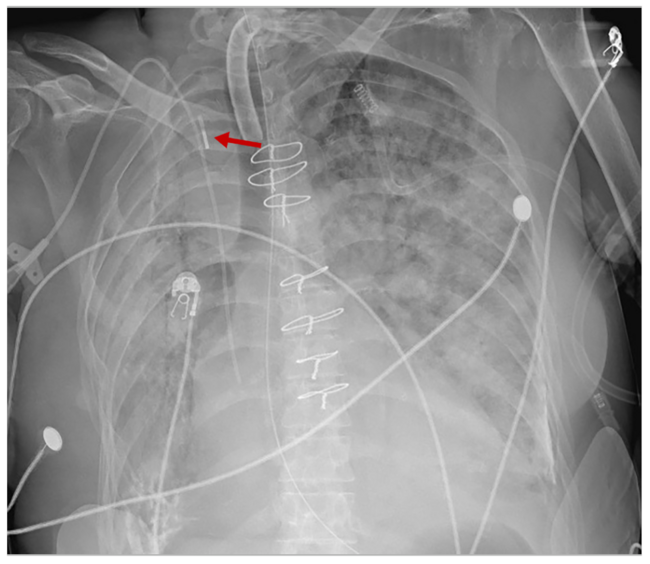

Cardiac arrest occurred 48 hours later, and a Lund University Cardiopulmonary Assist System was used to provide mechanical chest compressions, while emergent right femoral intra-aortic balloon pump (IABP) was placed at the bedside after confirmation of pulsatile blood return. Inflations at 1:1 were initiated and resuscitation efforts continued. The balloon pump waveform appeared abnormal with low mean and augmentation pressures (Figure 2), but this was attributed to ongoing hypotension or a technical problem related to the pump rather than position, because pulsatile blood return was noted at the time of right femoral access. It was not until a chest x-ray was performed that intra-caval placement of the balloon pump was identified and subsequently replaced in the femoral artery.

When performed emergently at the bedside, inadvertent intra-caval placement of a balloon pump can occur due to elevated venous pressures such as during cardiopulmonary resuscitation, in the presence of severe tricuspid regurgitation, or through an arteriovenous fistula. A similar radiographic appearance can also be seen in the presence of a right–sided aortic arch (Figure 3). Clues to improper position include an abnormal pressure waveform and the absence of hemodynamic changes or blood pressure augmentation.